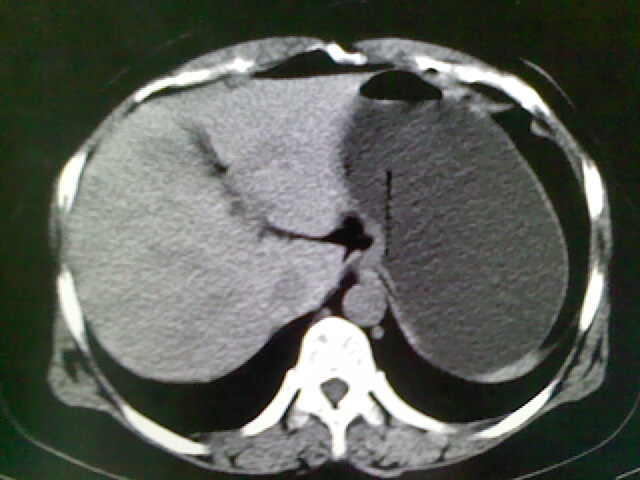

以下是引用卜一在2009-4-2 13:26:00的发言:[br]胆囊颈部结石伴胆囊炎!另:建议增强,待除外肝内占位及胆囊占位!

以下是引用liaoqiang在2009-4-2 16:23:00的发言:[br]胆囊是否切除?胆囊颈区致密影考虑金属夹?结石?肝脏右叶低密度影,考虑增强。